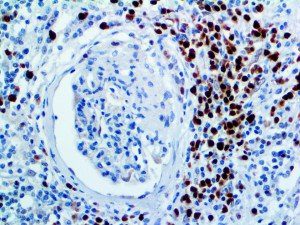

It is the ICU physician who is most likely to witness one of the deadliest manifestations of the abnormal immunological response, the cytokine storm syndrome (CSS). This response is also referred to by some as the cytokine release syndrome (CRS). CSS is characterized by continuous activation and expansion of macrophage and lymphocyte populations, which secrete large amounts of cytokines, causing the cytokine storm. This massive cytokine release is akin to hemophagocytic lymphohistiocytosis (HLH) disease, a syndrome characterized by initial unchecked and persistent activation of cytotoxic T lymphocytes and NK cells.

Clinical and laboratory manifestations of HLH include fever, enlarged liver and/or spleen, neurologic dysfunction, coagulopathy, liver dysfunction, cytopenias (i.e., low levels of erythrocytes, leukocytes, and/or platelets), hypertriglyceridemia, hyperferritinemia, hemophagocytosis, and eventually diminished NK cell activity as the immune system becomes progressively paralyzed. HLH can be familial (primary HLH) or secondary to another disease process (sHLH), such as rheumatic disease, in which it is referred to as macrophage activation syndrome (MAS, characterized by elevated ferritin).